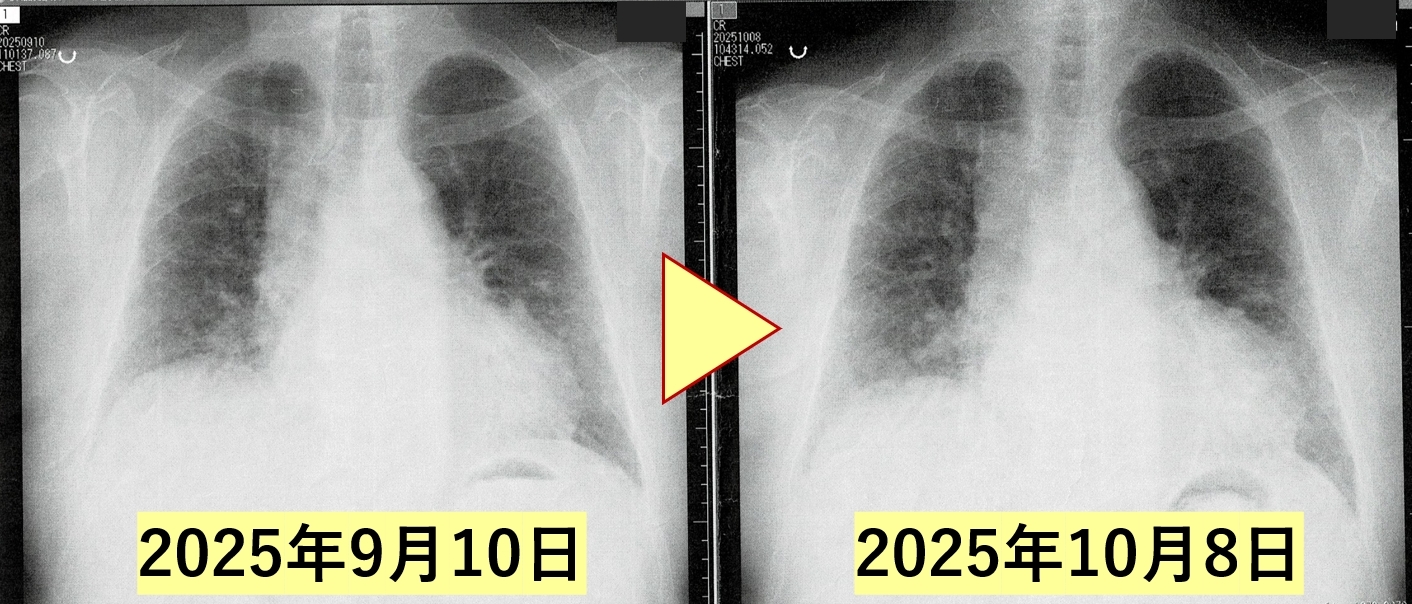

レントゲン検査/すりガラス陰影の改善